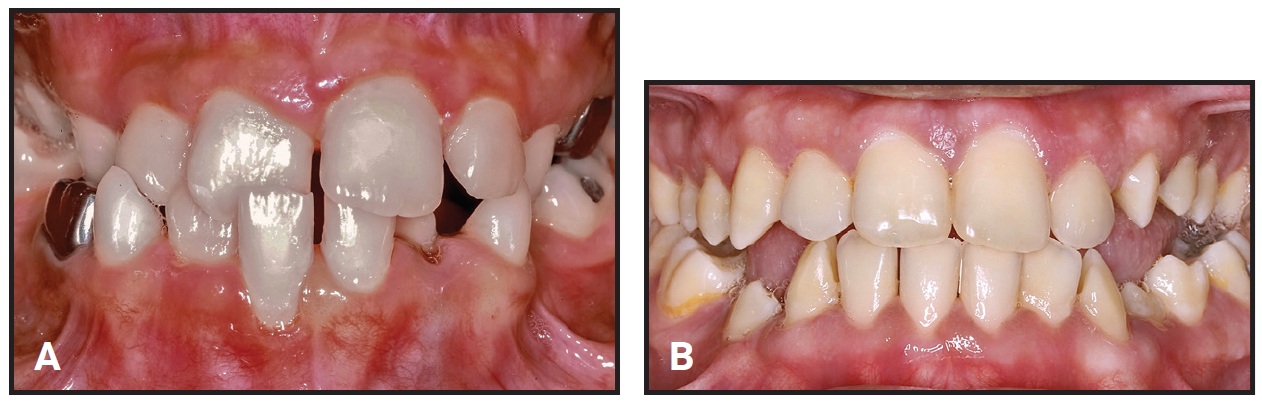

Fig. 3 Case 3. A. 9-year-old patient with crossbite before treatment. B. Two years later, showing improvement in gingival retreat after crossbite correction (six months of active treatment). Deciduous canines extracted to relieve crowding; no retention needed.

Retention is not needed when the overbite is complete. Any gingival retreat on the mandibular incisors will improve after crossbite correction2 (Fig. 3). Mandibular incisor irregularity often improves secondary to maxillary incisor alignment, provided adequate space is available.